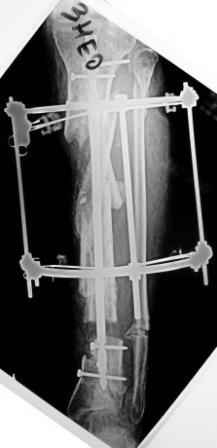

3) Третьим этапом наложили модуль на промежуточный фрагмент.(рис 3) И начали его транспорт на стержне в проксимальном направлении. (рис 3 а)

Надеемся что «вырастет» регенерат в дистальном отделе, а в проксимальном отделе фрагмент «упрется» и прирастет.